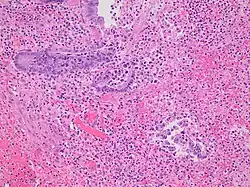

Pathology diagnosis of appendicitis can be made by detecting a neutrophilic infiltrate of the muscularis propria.

Micrograph of appendicitis and periappendicitis. H&E stain. -

Micrograph of appendicitis showing neutrophils in the muscularis propria. H&E stain. -

Acute suppurative appendicitis with perforation (at right). H&E stain.